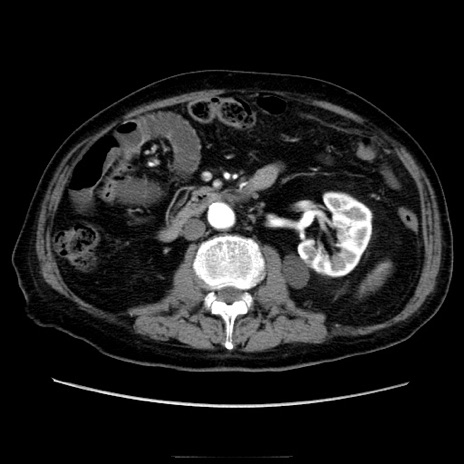

症例21(横断像)

【症例】70歳代男性

【主訴】腹痛

【現病歴】肝硬変・肝細胞癌にてかかりつけの方。約9時間前に食後より腹痛出現。症状が徐々に増悪し、嘔吐出現したため来院。

【既往歴】肝硬変、肝細胞癌(RFA、TACE後)

【身体所見】意識清明、表情苦悶様、BT 36℃、BP 129/78mmHg、P 88bpm、SpO2 97%(RA)、右上腹部から心窩部にかけて圧痛あり、反跳痛なし、筋性防御あり。

【データ】WBC 5800、CRP 0.16